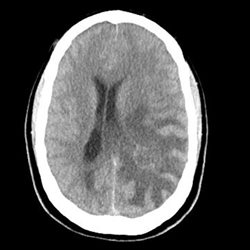

28 yo female presenting acutely with new onset headache and a seizure. But the prior history was unknown at the time of this admission. Later it was discovered the patient was diagnosed 5 years earlier with a left parietal AVM, which had been treated with intravascular embolotherapy and radiation. CT, CTA, MR